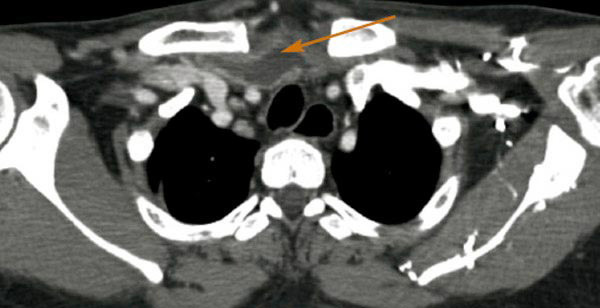

Cellulite cervico-médiastinale avec abcès rétro-sternal

Scanner en coupe axiale d'un patient présentant un abcès latéropharyngé droit.